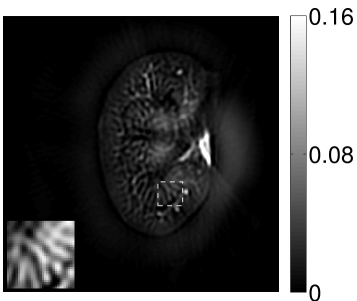

VI-E Results: kidney phantom

The images and EIRs reconstructed by use of the VP algorithm that was based on the 2D imaging model that neglected the SIR are shown in Figures 15 and 16. The latter figure contains results corresponding to different values for the regularization parameter . From Fig. 15, it can be observed that use of the conventional iterative method that utilized the measured EIR resulted in distortions and loss of details in the reconstructed images. Use of the VP algorithm improved the contrast and the details in the reconstructed images (Fig. 15(c) and 16(a)). Furthermore, the images reconstructed by use of the VP algorithm had a more uniform background.

In Figure 17, the results corresponding to use of the 3D imaging model that incorporated SIR effects are shown. The EIR estimated by the VP algorithm is also shown. In Figure 18, images and EIRs reconstructed by use of the VP algorithm with different regularization parameters values are shown.

Similar to the case described above where the transducer SIR was neglected, these results reveal that use of the VP algorithm can produce images with a cleaner background and enhanced spatial resolution than yielded by use of a conventional iterative algorithm that employed the measured EIR. For example, detailed information regarding the vessels near the organ’s periphery was better preserved by the VP algorithm than by the conventional iterative algorithm. These images corroborate our assertion that the VP algorithm can significantly reduce the artifacts and distortions in the reconstructed image. It is also worth pointing out that, unlike the numerical phantom studies, the artifacts and distortions in the images may be caused not only by the inaccurate EIR but also by other factors, such as neglecting acoustic heterogeneities and the variation of the EIRs among the elements of the transducer array. In such cases, the EIR estimated by the VP algorithm represents an effective system impulse response that minimizes the inconsistency between the measured data and the imaging model.